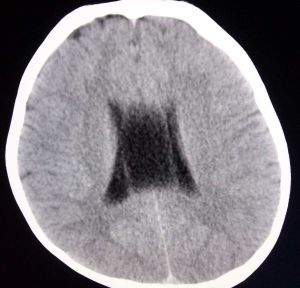

若兩側側腦室間的含液結構的兩側壁向兩側彎曲膨隆,且側壁間的距離大於或等於10mm,即為透明隔囊腫。

在CT或MRI上,透明隔的兩壁呈前後平行排列,直徑小於10mm,臨床無症狀,稱為透明隔腔。若在CT或MRI上,透明隔的兩壁向兩側彎曲膨隆,凸向兩側側腦室,兩壁間直徑大於等於10mm,多伴有可用該病變解釋的臨床症狀,稱為透明隔囊腫。透明隔囊腫與側腦室間不交通。

透明隔囊腫分為症狀性與非症狀性兩種,前者又稱為擴張性透明隔囊腫,它可造成室間孔的梗阻,產生頭痛、嘔吐、視乳頭水腫及意識障礙等顱壓增高症狀.當透明隔囊腫累及下丘腦-隔三角區或影響腦深部的靜脈回流時,可出現行為、自主神經以及感覺運動功能的異常.一旦發生腦積水,可壓迫視神經通路,引起神經眼科方面的症狀.根據MRI所見和臨床表現特點可確定診斷.套用腦的內窺鏡技術,施行透明隔囊腫-腦室造屢或分流手術,可解除梗阻性腦積水,迅速緩解臨床症狀。